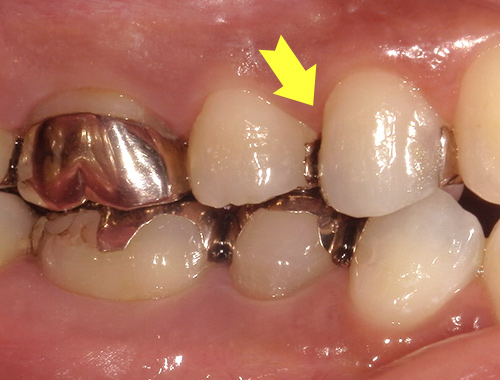

- 症例紹介

保険の被せ物をセラミック

(自費治療)に変更

保険診療で使われていた金属の被せ物を、自然な見た目のセラミッククラウンに変更した症例です。金属の被せ物は、強度が高く保険適用で治療できる一方で、見た目が目立ってしまったり、経年劣化により歯ぐきの黒ずみが出てくることがあります。

今回の症例では、金属の被せ物をセラミックに置き換えることで、まわりの歯と調和のとれた自然な色と形に仕上げました。口元の印象が大きく変わり、笑ったときにも金属が見えず、清潔感のある印象になります。

セラミックは金属を使わない素材のため、金属アレルギーの心配がなく、長期間の使用でも変色しにくいという特長があります。適合性も高く、歯とのすき間ができにくいため、むし歯の再発リスクも軽減されます。

銀歯の見た目が気になる方や、より自然で美しい仕上がりを求める方には、セラミックによる被せ物の治療をおすすめしています。気になることがあれば、まずはお気軽にご相談ください。

治療期間通院3回(むし歯治療、型取り、セット)、約3週間程度

費用目安税込132,000円